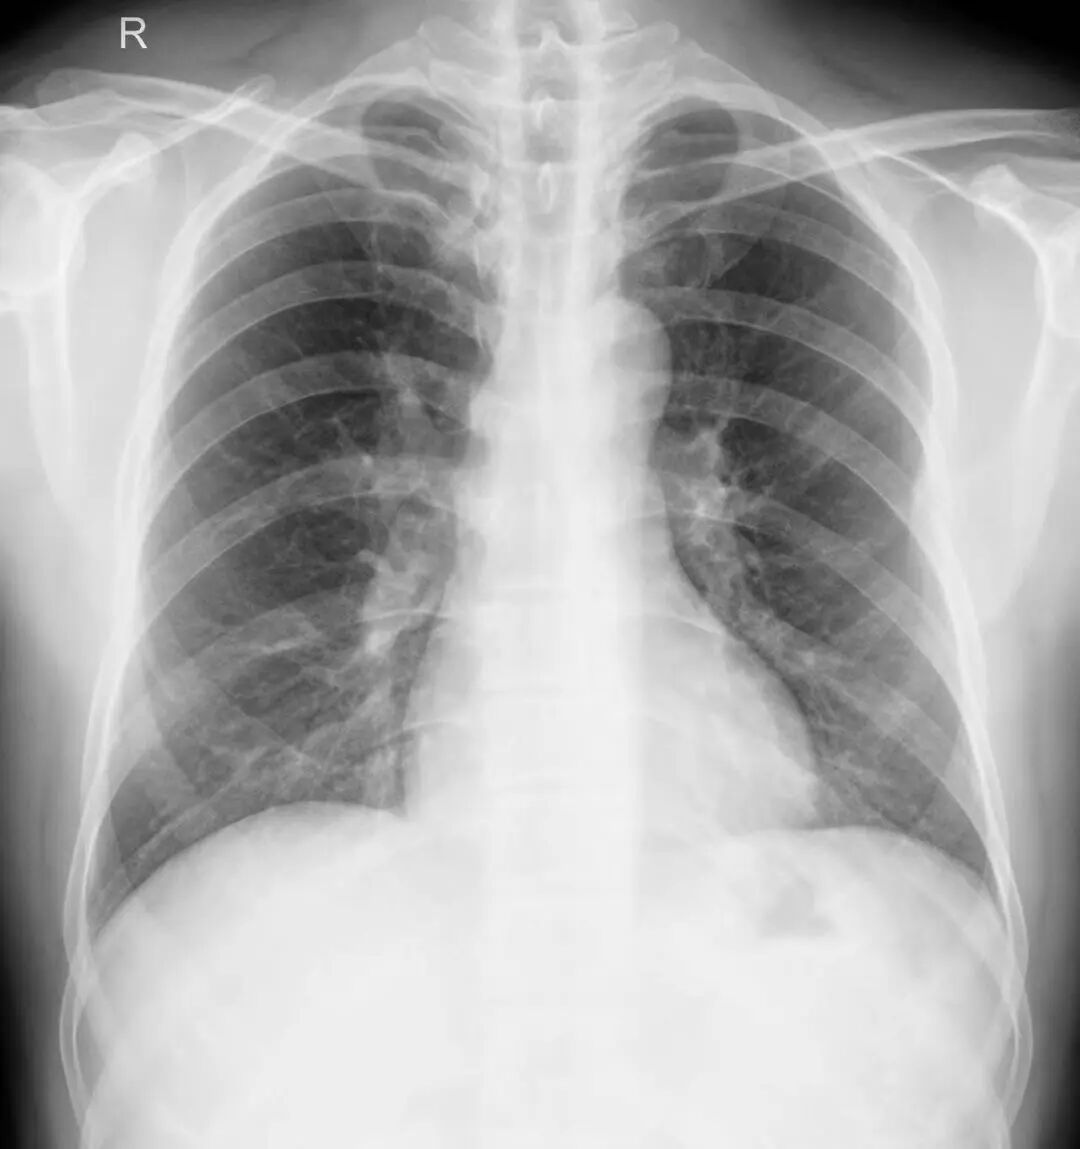

X线摄影,俗称拍片子。它的原理是“拍扁了”看,这样就有可能造成组织或器官的重叠,导致病变部位隐藏或显示不清。

CT扫描是一层一层的看,还可以重建冠状位、矢状位更仔细的观察。避免组织间的重叠,大大提高确诊率,降低漏诊的可能性。

X线检查作为常规检查方法,费用低、辐射量小,能够对疾病迅速定位。

在就诊过程中,临床医生会根据实际病情首选X线检查。

平片发现了病变,但不能定性、定位,无法观察其具体形态时。需进行CT扫描对病灶进行定性,同时了解病变与周围组织的关系,进而确定下一步的治疗方案。

外伤患者进行了X线检查后,平片上发现异常,但对病灶观察不够全面时。需通过CT检查的后期重建进行多方位观察。

综上所述,两种检查各有优势、互相补充、不可替代。具体做什么检查,需要根据病情而定。